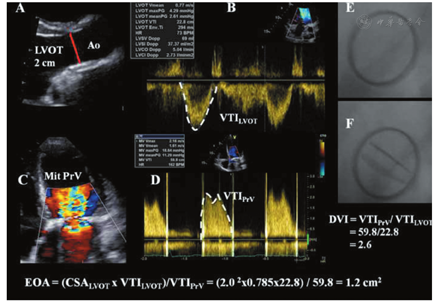

与跨瓣速度或压差相比,人工瓣膜EOA较少受血流的影响,因而是评价瓣膜内在血流动力学性能的更可靠指标(表1,表2)[19]。然而,这一参数更易出现技术性误差和测量误差。对人工主动脉瓣和人工二尖瓣来说,应该采用LVOT或偶尔右心室流出道(RVOT)测得的每搏量根据连续性方程法计算EOA(图7,图8)[106,111,112]。EOA反映的是跨人工瓣射流束(缩流束)的最小横截面积(CSA),计算公式:

EOA=CSA×VTILVOT/VTIPrV=0.785×(DLVOT)2×VTILVOT/VTIPrV

EOA = Stroke volume/VTIPrV

其中VTILVOT是指跨LVOT的血流速度时间积分,在LVOT内主动脉瓣(心尖切面)或偶尔肺动脉瓣(短轴切面)的近心端应用脉冲波(PW)多普勒测量获得;VTIPrV是应用连续波(CW)多普勒测量的跨人工瓣速度时间积分。很少用肺动脉瓣计算每搏量,但在LVOT无法评价时可以采用[19]。

连续性方程法要求用来计算每搏量的速度为空间平均速度,后者是通过将取样容积从人工瓣环向LV心尖部移动0.5~1.0 cm获得的[19]。基本原则是LVOT的直径和速度测量几乎来自同一解剖位置。如果频谱中包含清晰的频谱轮廓和人工瓣膜的关闭喀喇音(以人工主动脉瓣为例),提示取样容积位置最佳。通过描记多普勒信号轮廓获得VTI。在连续性方程法中可以用峰值速度代替VTI[19]。VTIPrV从同一探头位置记录(TTE采用心尖五腔心或三腔心、胸骨右旁或胸骨上窝切面;TOE采用经胃90°~120°切面或经胃底倒置切面0°~20°)。由于人工瓣膜组件产生的回声和声影,在人工主动脉瓣患者LVOT直径测量(TTE胸骨旁长轴放大切面或TOE 120°切面)往往比较困难。特别要注意的是,勿将人工瓣环的内边界误认为LVOT的内侧缘。任何LVOT直径的测量误差在计算EOA时都将被平方放大。如LVOT直径为2.0 cm,出现10%的测量误差(1.8 cm),将导致19%的EOA计算误差。需要强调的是,在连续性方程法中采用标记的人工瓣膜尺寸替代LVOT直径测量来评估人工主动脉瓣EOA是不可靠的[112]。对于人工主动脉瓣,当存在瓣膜反流时,连续性方程同样有效。然而,对于人工二尖瓣,当合并轻度以上的二尖瓣反流(MR)或主动脉瓣反流(AR)时,不能利用连续性方程法计算EOA。在某些情况下,当传统的2D多普勒方法不可行/不可靠时,可以采用容积法。在功能正常的人工瓣膜中,EOA测值应在根据瓣膜类型和型号区分的正常参考值范围内(表7,表8)。